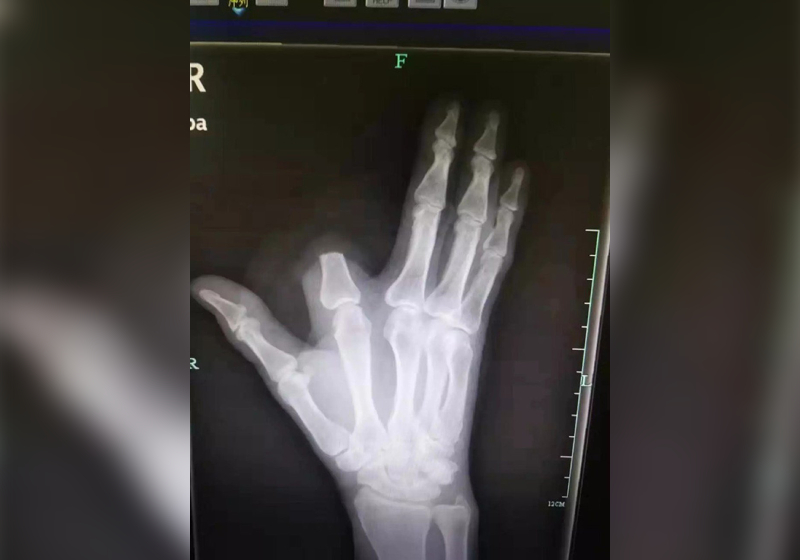

Ông Zhang đã tự chặt phăng ngón tay vì sợ độc tính lan rộng.